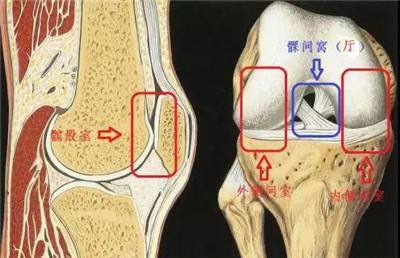

膝关节的三个间室以及髁间窝示意图

根据解剖特点,膝关节按空间可分为内侧间室、外侧间室、髌股关节间室和髁间窝。膝关节置换手术的范围包括股骨远端和胫骨远端相对应的关节面(双间室置换术),部分还包括髌股关节面(三间室置换术)。但如果患者的膝关节退化仅涉及膝关节内侧单间室,这时候就可以考虑行微创膝关节单髁置换术(单间室置换术)了。但是单间室置换术适应症较局限,手术前必须经过详细的检查才能确定患者是否符合手术指征,而非每个膝关节骨性关节炎的患者都适合手术。下面我们来看一下究竟有哪些条件: